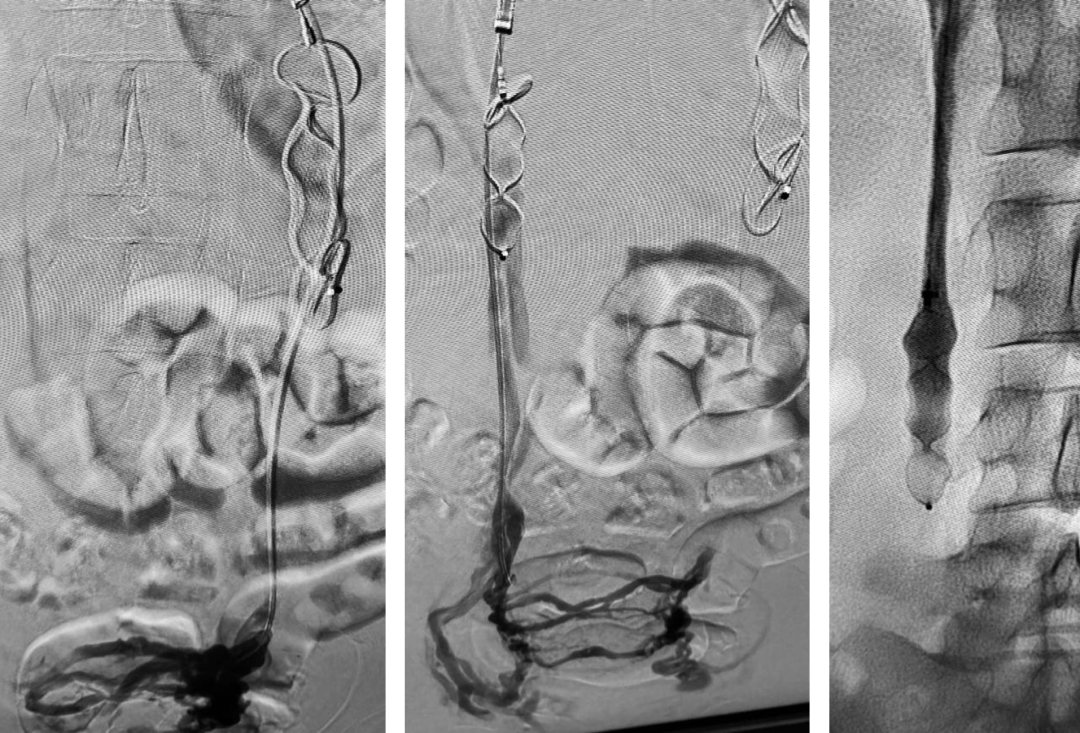

结合机械栓塞和硬化治疗联合处理的现有技术中,三明治技术是较常被使用的技术:导管深入至最低,在逐步后撤的过程中由远至近、由下至上依次间隔置入弹簧圈和硬化剂两种不同的栓塞材料,硬化和栓塞多点阻断。该技术优势为操作相对简便,但也存在一些缺陷。高压锅技术(Pressure Cooker Technique)是神经介入中经常使用的技术。既保护了流出血管,又保证了病变部位的低压处理。故而我们尝试改进技术:近端弹簧圈/Amplatzer血管塞(AVP)致密栓塞+后续远端硬化治疗。可以即刻确认近端阻断程度,可以即刻观察到完全阻断后的远端血流状态,可以在低流速环境下充分破坏病灶内皮。近端Amplatzer血管塞(AVP)+远端硬化治疗盆腔静脉功能不全病例见图3。

图片

图3. 近端Amplatzer血管塞(AVP)+远端硬化治疗盆腔静脉功能不全